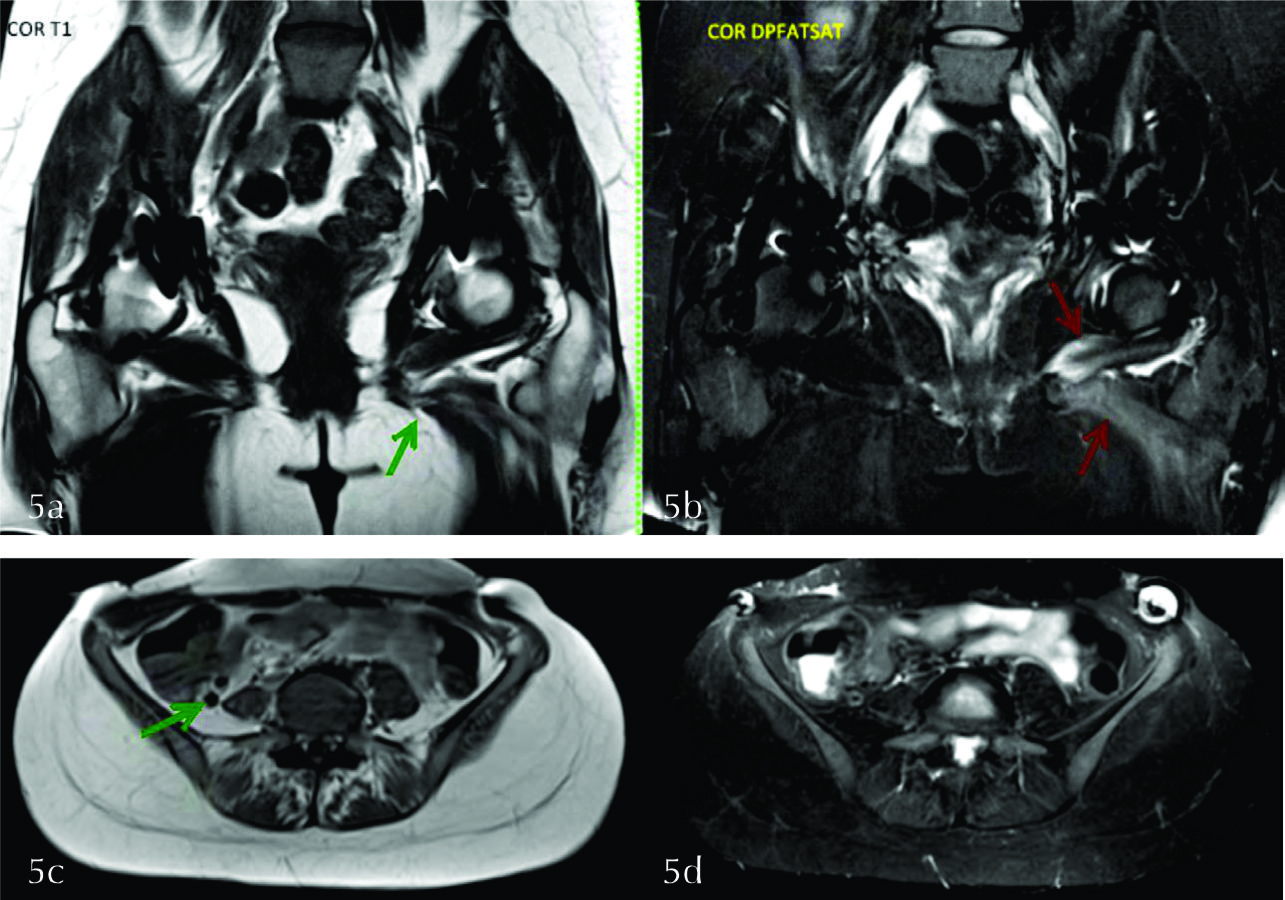

Paciente de 28 años, SF, con antecedente de displasia congénita de cadera bilateral que fue sometida a cirugía de cadera derecha en abril de 2016 con lesión de nervio femoral. En setiembre de 2016 fue intervenida de cadera izquierda y se le solicita RM por sospecha de lesión de nervio femoral a izquierda.

Se observan artefactos en ambas caderas en relación a los antecedentes quirúrgicos.

A izquierda se visualiza edema en el músculo obturador externo y aductores, con atrofia de los mismos, compatible con denervación subaguda en territorio del nervio obturador (fig. 5 a y b).

A derecha se observa atrofia del músculo psoas, sin edema, compatible con signos de denervación crónica por secuela de lesión del nervio femoral (fig. 5 c y d).

Dados los hallazgos se planteo lesión post quirúrgica del nervio obturador izquierdo en fase subaguda y del nervio femoral derecho en fase crónica.

En la figura 6 se muestra la topografía del nervio obturador.

Figura 5

a y b) Imágenes coronales donde se evidencian artificios en ambas caderas en relación a los antecedentes quirúrgicos. Se visualiza edema en los músculos obturador externo y aductores a izquierda (flechas rojas en b), con disminución de tamaño de los mismos en secuencia T1 (flecha verde en a). c y d) Se observa atrofia del psoas derecho, sin edema (flecha verde).